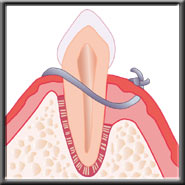

Scaling removes plaque & calculus |

Root planing smoothes the root surface |